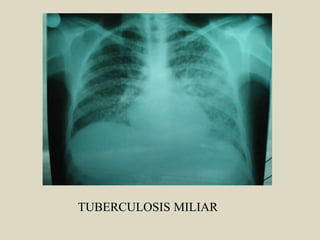

Criterios Radiológicos

diagnóstico

TUBERCULOSIS MILIAR